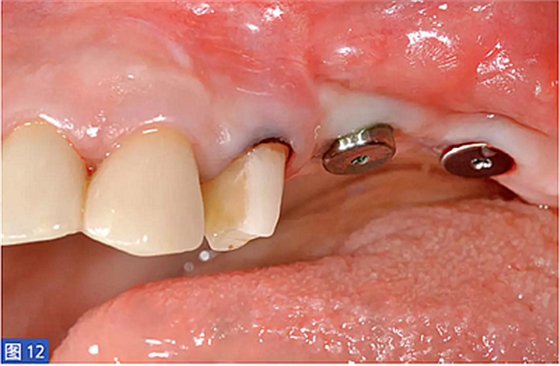

圖12:(右側(cè))病例2. 術(shù)后6個(gè)月,2顆種植體植入再生區(qū)域。